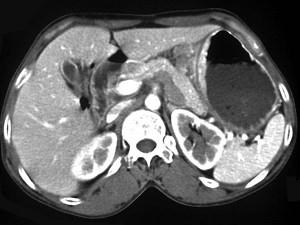

问题 女,56岁,上腹部钝痛、腹胀不适一月余,纳差、消瘦,影像检查如图,最可能的诊断是 ( )

选项 A、胃间质瘤 B、胃恶性间质瘤 C、胃腺癌并幽门狭窄 D、胃淋巴瘤 E、胃幽门管溃疡

答案 C